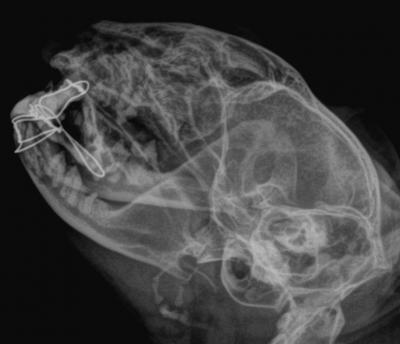

Jako základ fixátoru byly založeny cerkláže chirurgickým drátem. U dolní čelisti byl drát veden nejen kolem zubů, ale také pod kůží kolem celé čelisti. V horní čelisti byl nejdříve vyvrtán otvor kostí v místě vyraženého špičáku. Druhý špičák s okolní odlomenou kostí byl přitáhnut smyčkou vedenou skrz vyvrtaný otvor. Vzhledem k šikmému lomu měl fragment tendenci posunovat se dopředu, proto byl ve správné pozici upevněn ještě drátem uchyceným za stoličku.

Následně jsme provedli zbroušení fixačního aparátu, aby byl Vilibald schopen přijímat potravu. Fixační aparát byl ponechán po dobu šesti týdnů.

Na drátěný základ byl následně aplikován dentální akrylát, který vytvořil pevný fixační aparát.

RTG snímek dutiny ústní po provedení chirurgické rekonstrukce čelisti.